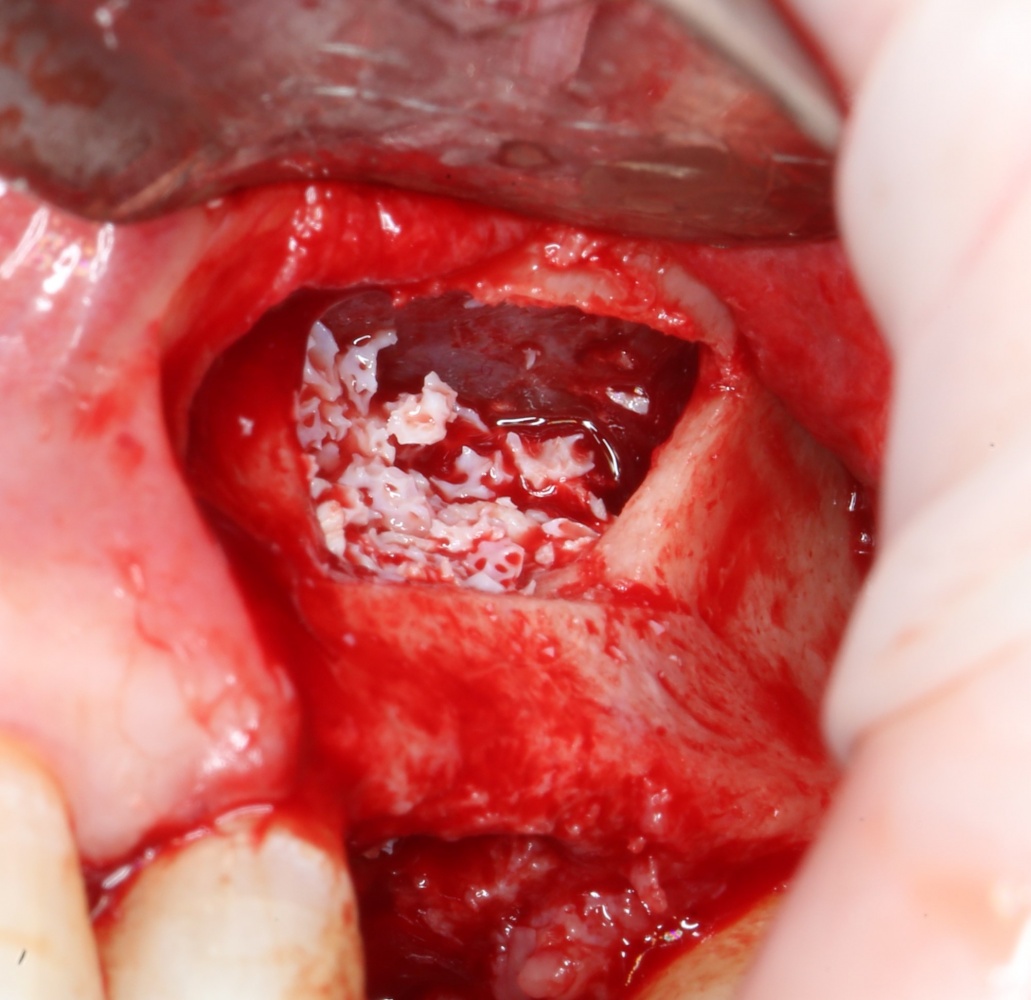

Для получения костного блока, мы открываем донорскую зону, наружную косую линию нижней челюсти.

Получение костного аутотрансплантата.

Здесь потребуется пародонтологический зонд с миллиметровой разметкой или какой-то другой измерительный прибор (операционная линейка). Ранее по КЛКТ я измерил костный дефект, теперь нужно нанести границы будущего костного блока на донорскую зону.

Для получения костного блока мы использовали ультразвуковую пьезохирургическую систему. Это самый удобный и безопасный инструмент для проведения подобных манипуляций. С помощью него мы сформировали и выделили костный блок. Он должен отделяться легким движением остеотома или элеватора. Как это сделать правильно — читай здесь>>